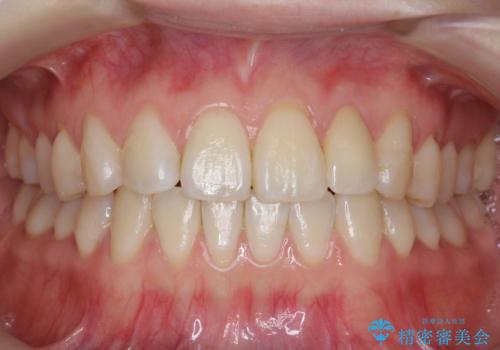

左上の前歯が飛び出しており、唇が笑った時に引っかかっていたのが解消しています。

左上の前歯は小さいため、(矮小歯)左右対称になるようにセラミックで形を修正する治療も併用しています。

左にずれていた上の正中も揃い、大変喜んでいただきました。